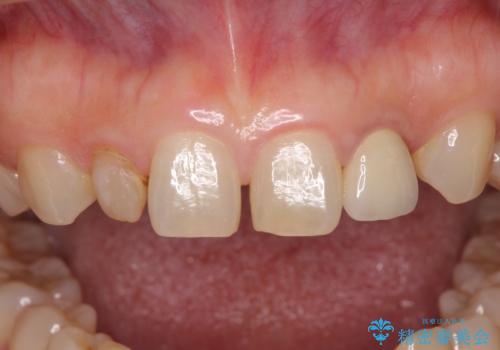

- 前歯の矮小歯に貼り付けられていたラミネートベニアが外れてしまったとのことで来院された患者様です。

反対側の矮小歯は裏打ちが金属であったため、両方の歯ともにオールセラミッククラウンにて補綴することとしました。